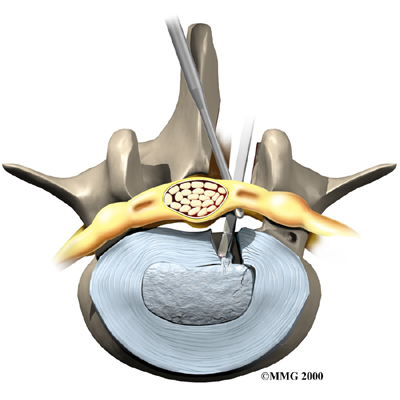

Microdiscectomy

Microdiscectomy is becoming the standard surgery for lumbar disc herniation. The procedure is used when a herniated disc is putting pressure on a nerve root. It involves carefully taking out part of the problem disc (discectomy). By performing the operation with a surgical microscope, the surgeon only needs to make a very small incision in the low back. Categorized as minimally invasive surgery, this surgery is thought to be less taxing on patients. Advocates also believe that this type of surgery is easier to perform, that it prevents scarring around the nerves and joints, and that it helps patients recover more quickly.

Related Document: FYZICAL Albany's Guide to Lumbar Discectomy